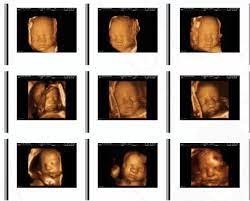

Sweet Baby Face 3d 4d Ultrasound

Sweet Baby Face 3d 4d Ultrasound. Book an appointment in Louisville or Elizabeth today. We Specialize in 4DHD Ultrasound 3D Ultrasound Photography and Baby Boutique items.

Sweet Baby Faces Ultrasound Studio. The entire scanning session video will be provided via email for unlimited sharing with friends and family. 1479 likes 26 talking about this 691 were here. Now you can see your baby up close and personal with a 3D4D HD ultrasound from Sweet Baby Face.